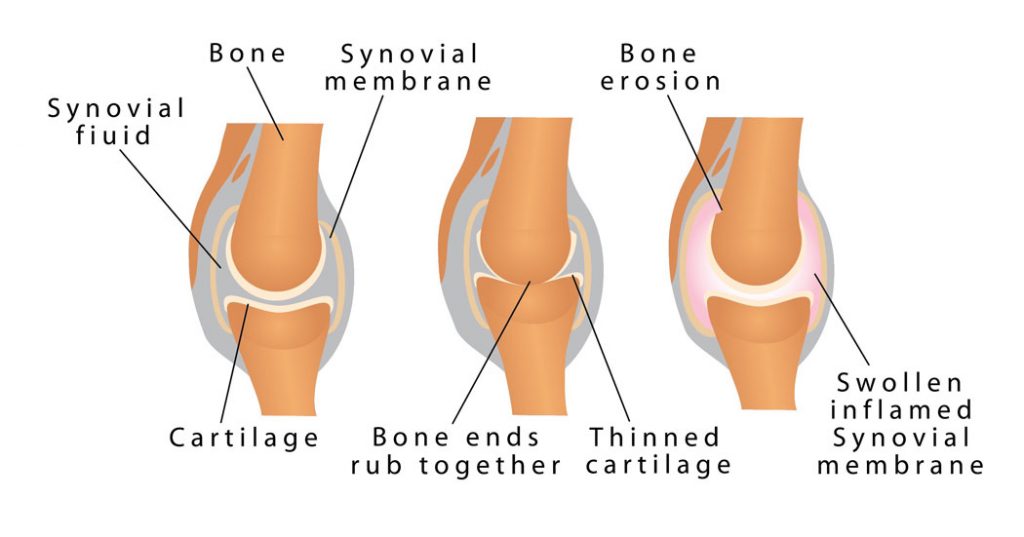

Finger arthritis is an inflammatory disorder that can occur in many different ways. It can be systemic where your body will attack itself in the case of Rheumatoid Arthritis (RA) or it may occur as a result of wear and tear, Osteo Arthritis (OA). While both of these conditions are painful and involve swelling and the de generation of the cartilage insie the joints of the finger, their cause is very different. At Action Rehab our Hand Therapists assess and treat a majority of patients who suffer from Osteo Arthritis (wear and tear of the joints) which often occurs as a result of a sporting or repetitive job or task such as gardening. This type of arthritis is very common and can be easily treated. Finger arthritis is painful and it is debilitating and can cause deformities if left untreated. At Action Rehab our Hand Therapists, Physiotherapists and Occupational Therapists are experienced in reading x-rays and assessing your hand for arthritis and joint degeneration.

It may be due to the presence of Rheumatoid Arthritis (RA). RA can cause the erosion of tendon and joint cartilage and results in your fingers being pulled towards your little finger (ulna side) of your hand. An MCP ulnar drift splint may help you to reduce your pain, increase your function and help make a fist. A resting night splint can help to prevent further ulnar drift. At Action Rehab we have experience in both of these splints and are here to help you.

It is caused by inflammation and degeneration of the joint that damages the cartilage.